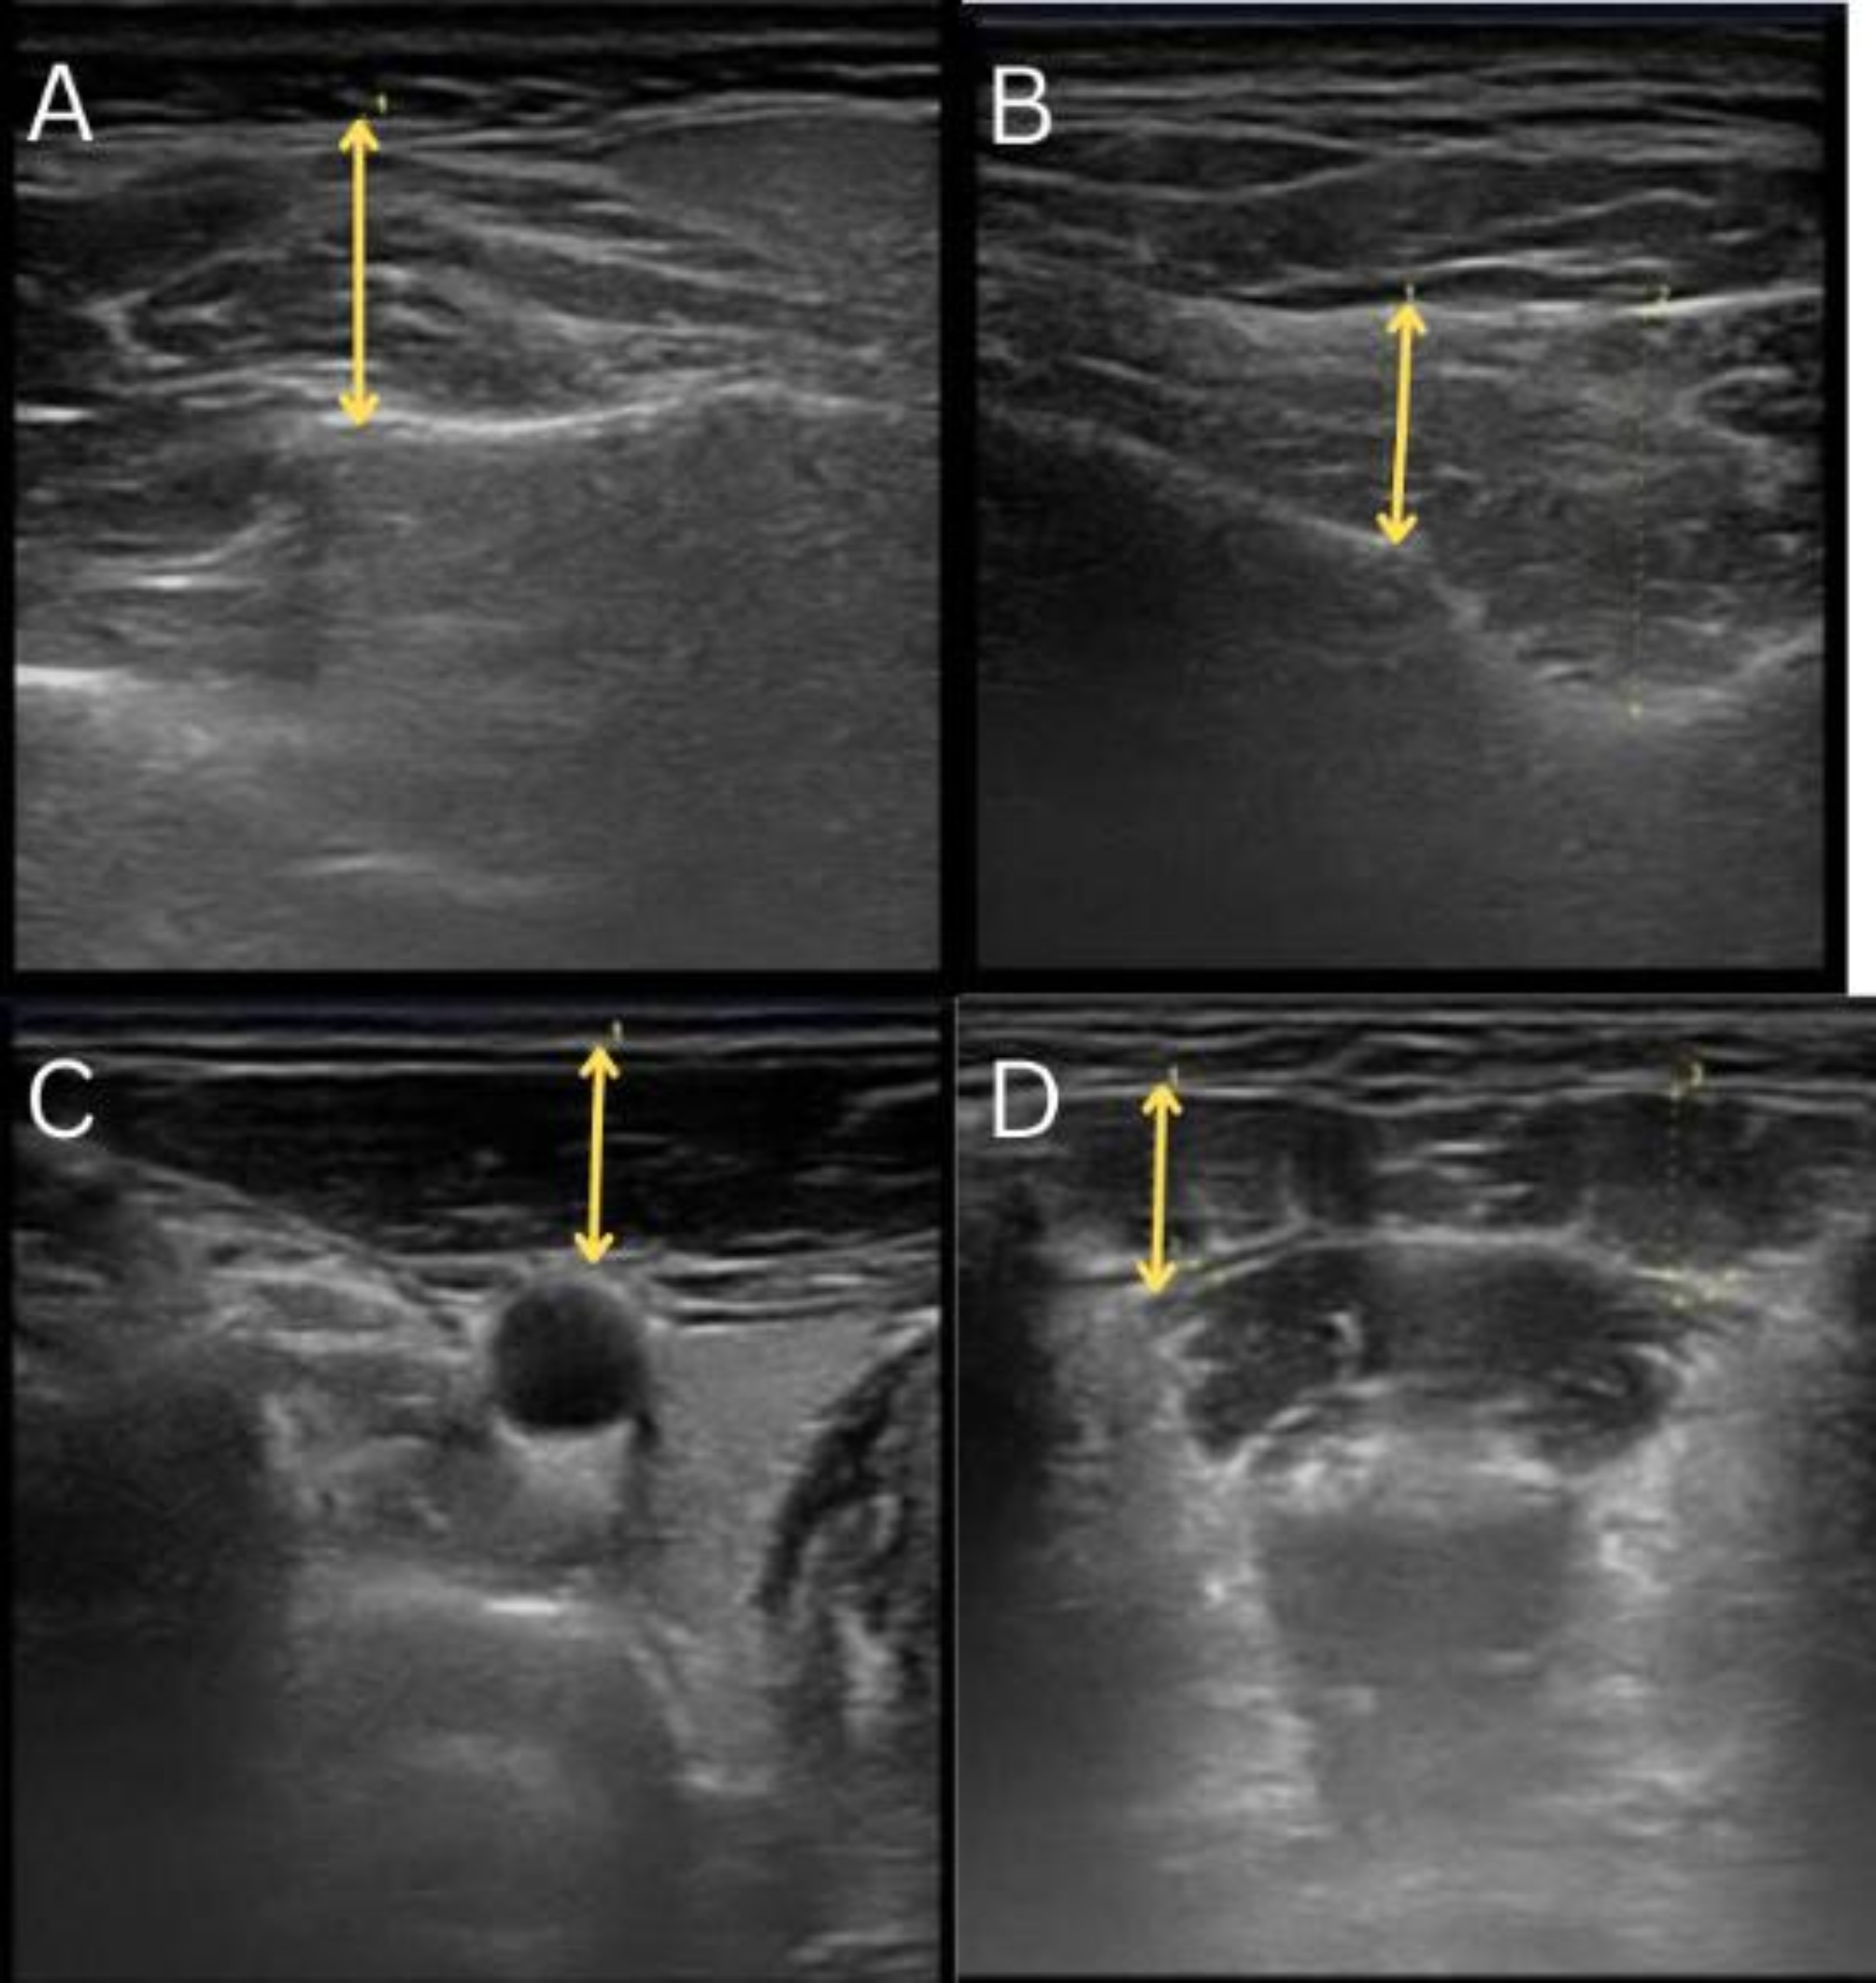

Objective: This study aimed to assess the thickness and ultrasonographic pattern of the masticatory and suprahyoid muscles in OSA patients and compare the effects of mono-bloc (MB) and bibloc (BB) mandibular advancement devices (MADs) via ultrasonographic measurements.

Methods: This pilot study of 20 patients with mild-to-moderate OSA who were diagnosed by full-night polysomnography (manually scored by the American Academy of Standards and Methods (AASM) manual, version 2.4) and treated randomly with mono-bloc or bibloc MAD (n = 10). The baseline thickness and pattern (types I, II, and III) of the masticatory and suprahyoid muscles were assessed by an oral radiologist. The same procedure was repeated at the 3-month and 6-month follow-up time points for participants after appliance use.

Results: Both types of MAD devices significantly increased the thickness of all muscles (p < 0.05). The changes in ultrasonographic muscle patterns were significant only in the BB group for the SCM muscle (p = 0.006). no other significant changes were observed in the studied ultrasonographic muscle patterns in the MB and BB devices up to 6 months (P > 0.05). No significant differences in muscle thickness or patterns were detected between the MB and BB modalities (P > 0.05).

Conclusion: The results of the present study indicate that MAD treatments do not have contraindications based on changes in muscle thickness and ultrasonographic muscle patterns. However, the BB group showed significant changes in the SCM ultrasonographic muscle pattern. Nevertheless, further studies are required to validate these findings.